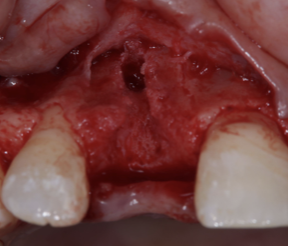

② インプラント埋入手術

抜歯後の治癒期間を経て、骨の状態を確認しながらインプラントを適切な位置と角度に埋入しました。

前歯部は見た目に大きく関わる部位のため、インプラントの位置・角度・歯ぐきの厚みを慎重に考える必要があります。

歯ぐきの移植を行った理由|清掃性・審美性・長期安定のために

今回の症例では、感染により骨や歯ぐきの一部が失われていました。

そのため、インプラント周囲の歯ぐきの厚みと形を整える目的で、結合組織移植術を行いました。

前歯のインプラントでは、ただ噛めるだけでなく、自然な見た目や清掃しやすさも重要です。

歯ぐきに厚みを持たせることで、見た目の調和を図り、インプラント周囲を長期的に安定させやすくなります。